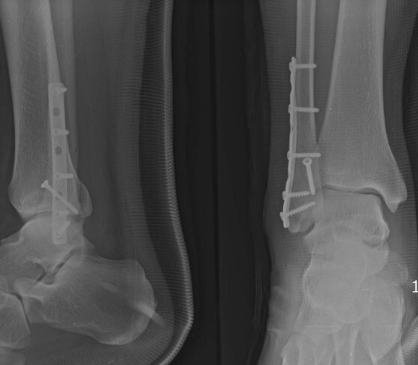

3. 골절

발목 골절은 발목 뼈 중 하나 이상이 부러진 경우를 말합니다. 이는 추락, 사고 또는 스포츠 부상과 같은 다양한 이유로 발생할 수 있습니다.

치료 방법 :

- 캐스트, 스플린트 또는 브레이스로 고정합니다.

- 일부 경우에는 부러진 뼈를 다시 정렬하고 안정화하기 위해 수술이 필요할 수 있습니다.

- 힘과 기동성을 되찾기 위한 물리 치료가 필요할 수 있습니다.